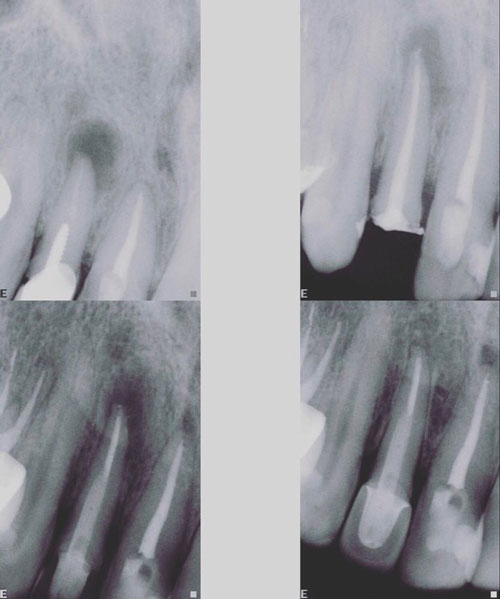

1) Εξέταση και διάγνωση με διάφορα διαγνωστικά τεστ και λήψη ακτινογραφίας.

7) Αν το δόντι είναι ασυμπτωματικό και ο ασθενής δεν πονά η απονεύρωση μπορεί να ολοκληρωθεί με την έμφραξη των ριζικών σωλήνων με ειδικό εμφρακτικό υλικό, που λέγεται γουταπέρκα. Η γουταπέρκα μαζί με ένα φύραμα τοποθετείται στο εσωτερικό των ριζικών σωλήνων και τους εμφράσσει ερμητικά. Η έμφραξη πρέπει να εκτείνεται σε όλο το μήκος της ρίζας του δοντιού και να είναι συμπαγής.

Επιπλέον, το οδοντιατρείο DAC διαθέτει ψηφιακό ακτινογραφικό μηχάνημα για ελαχιστοποίηση της ακτινοβολίας και άμεση εμφάνιση των ακτινογραφιών κατά τη διάρκεια της απονεύρωσης καθώς και ψηφιακό εντοπιστή ακρορριζίου για εύκολη και γρήγορη απονεύρωση με ακρίβεια στη μέτρηση του μήκους της ρίζας και αποτελεσματικότερο καθαρισμό.